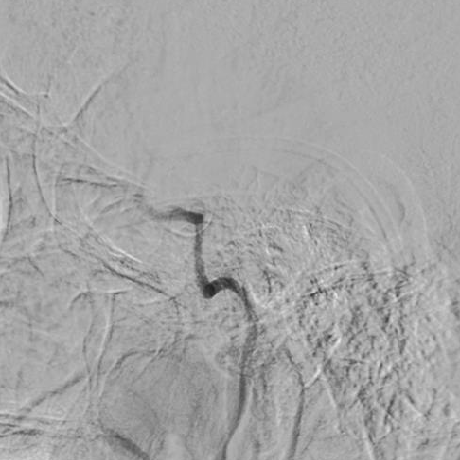

3、造影可见左侧颈内动脉前向血流恢复,M1段以远显影良好,眼动脉段可见重度狭窄,观察5分钟后,再次造影,眼动脉段以远血流速度明显下降,局部造影剂滞留,考虑与对侧前交通动脉的代偿供血形成湍流,有再次形成血栓的可能,遂对狭窄部位进行球囊扩张。

4、将微导丝+微导管小心通过狭窄部位,至于LMCA M1段,手推造影剂示真腔,撤出微导丝,送入长交换导丝撤出微导管,沿微导管送入赛诺2.0×10mm-152.8cm球囊至狭窄处,7atm充盈球囊及回抽,造影见狭窄较前改善,残余狭窄10%,远端血流速度改善,观察10分钟后造影见远端血流无明显变化。

术后患者症状明显减轻,NIHSS评分2分。第二天复查MRA,血管保持通畅。